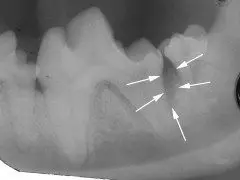

Surgical treatment of periodontal disease.

In some cases, deeper areas of periodontal disease with bone loss can be surgically treated to regenerate the bone, heal the void under the gum line and save important teeth. This form of treatment, termed “open root planing”, creates an environment for the normal supporting tissues of the tooth to regenerate.

Dental radiograph of this left lower first molar shows a large area of missing bone (arrows) due to long-term infection under the gum line. Treatment of this large chewing tooth is preferred to the trauma of extraction.